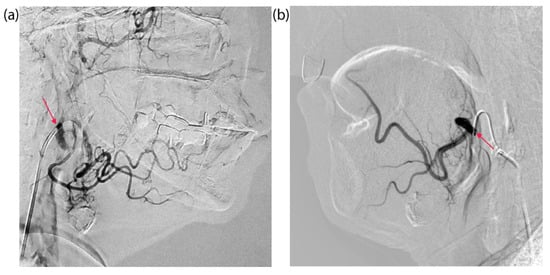

4.2. Tumor Catheterization